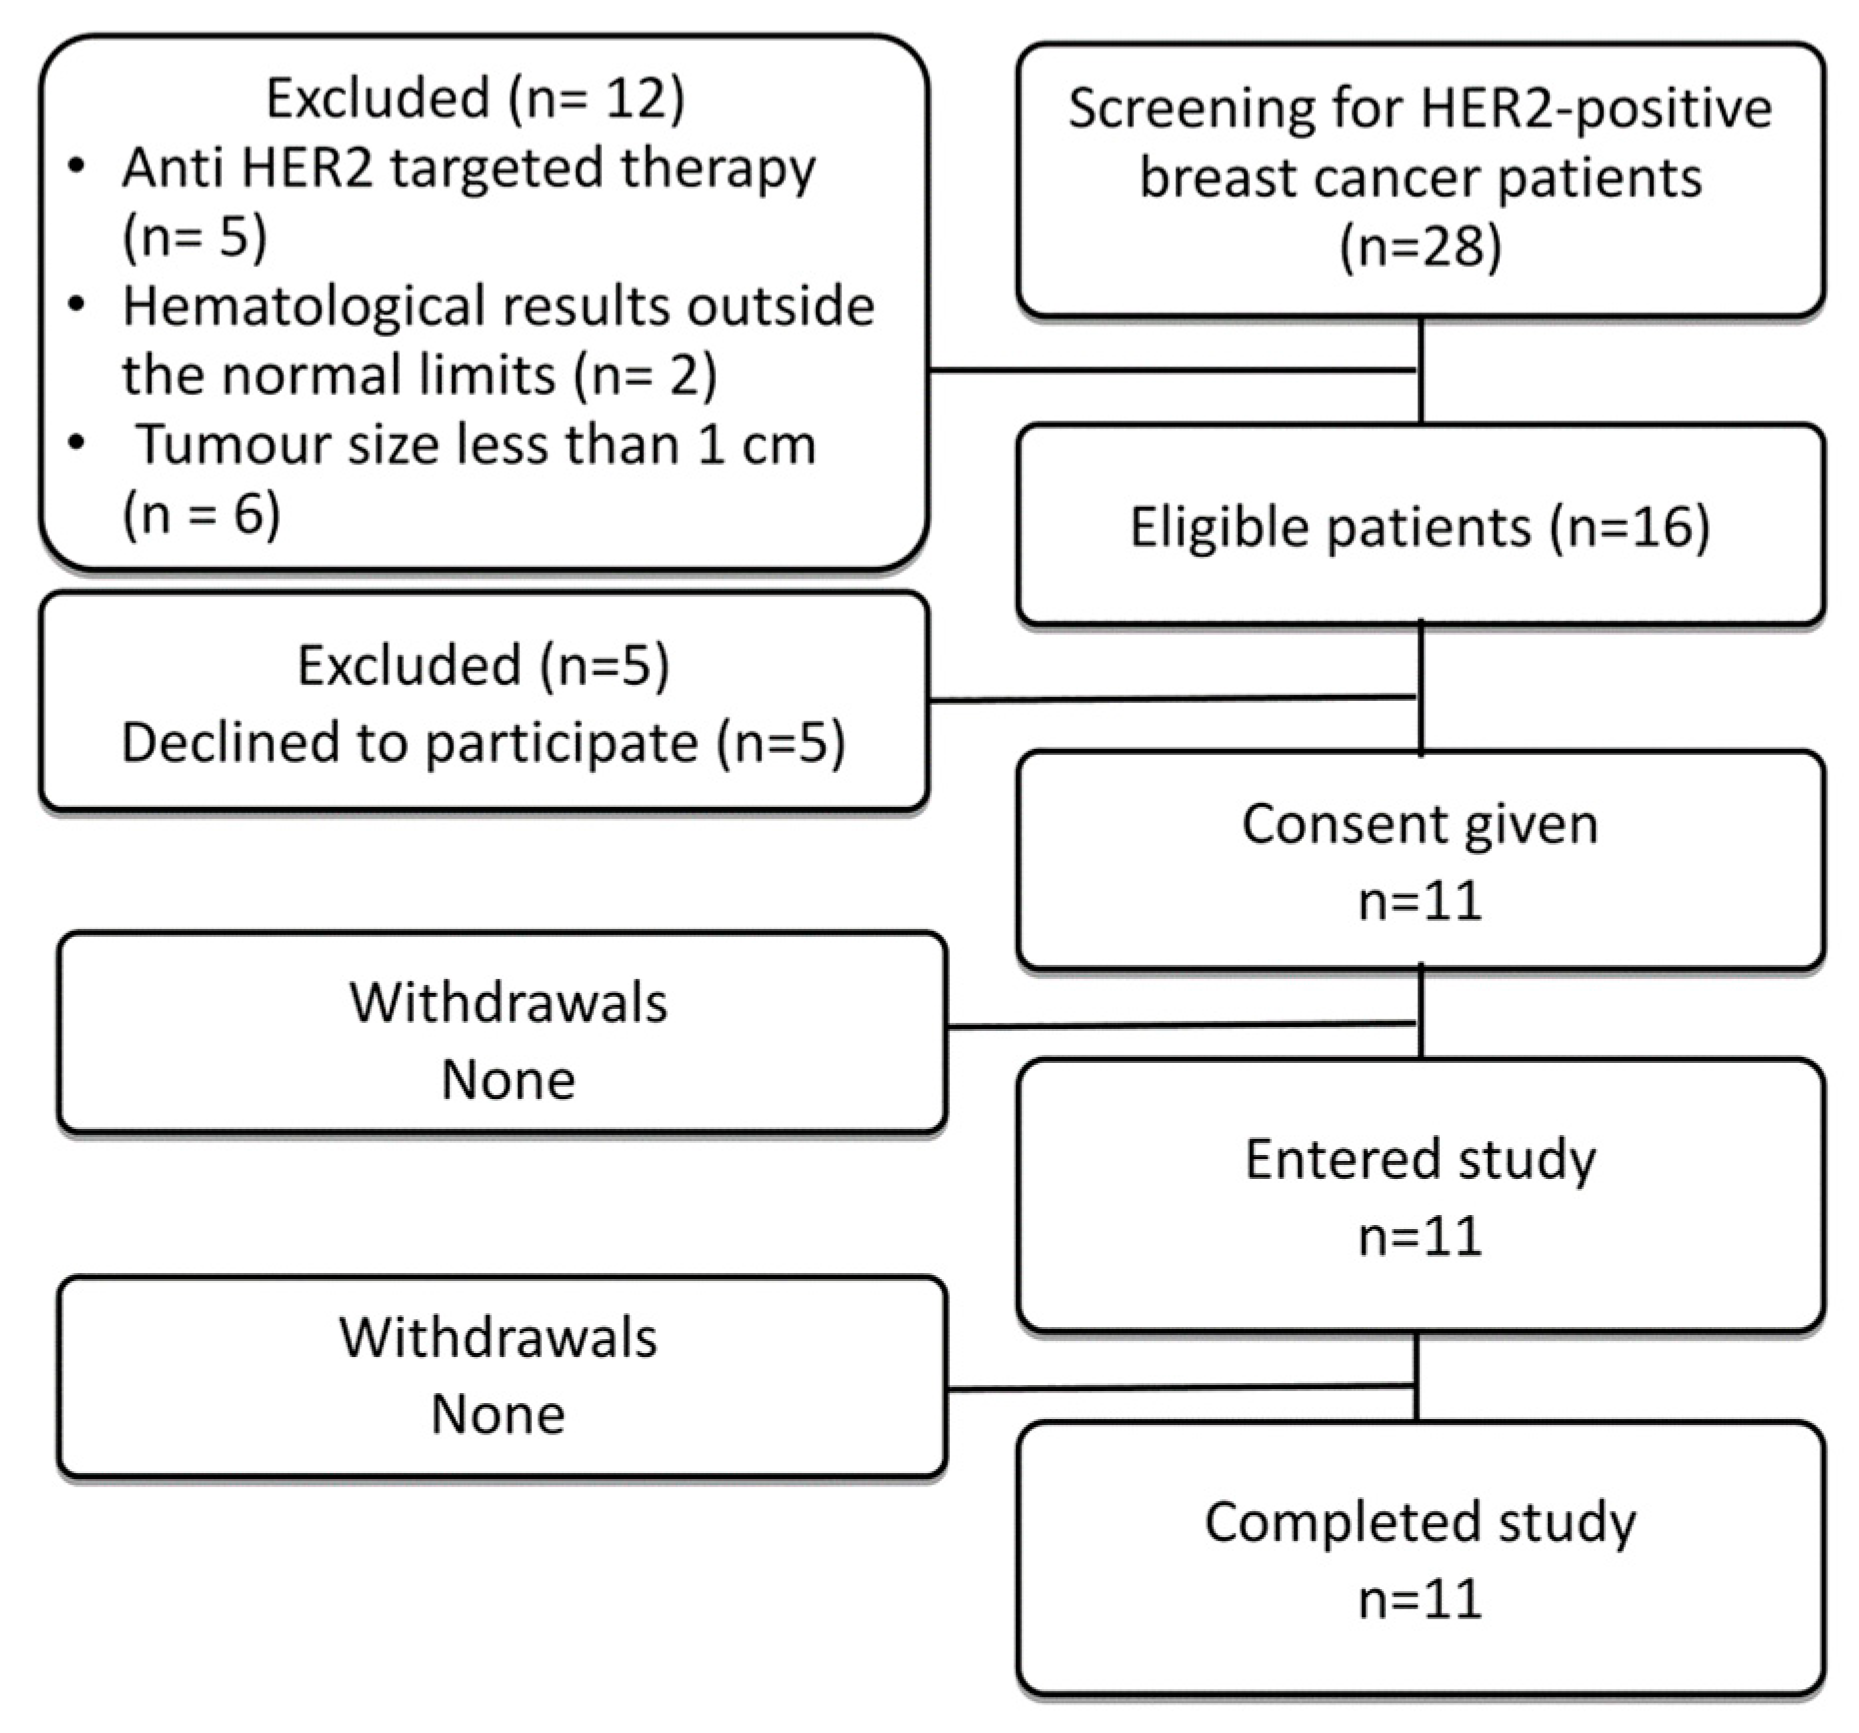

2. Materials and Methods

2.1. Patients